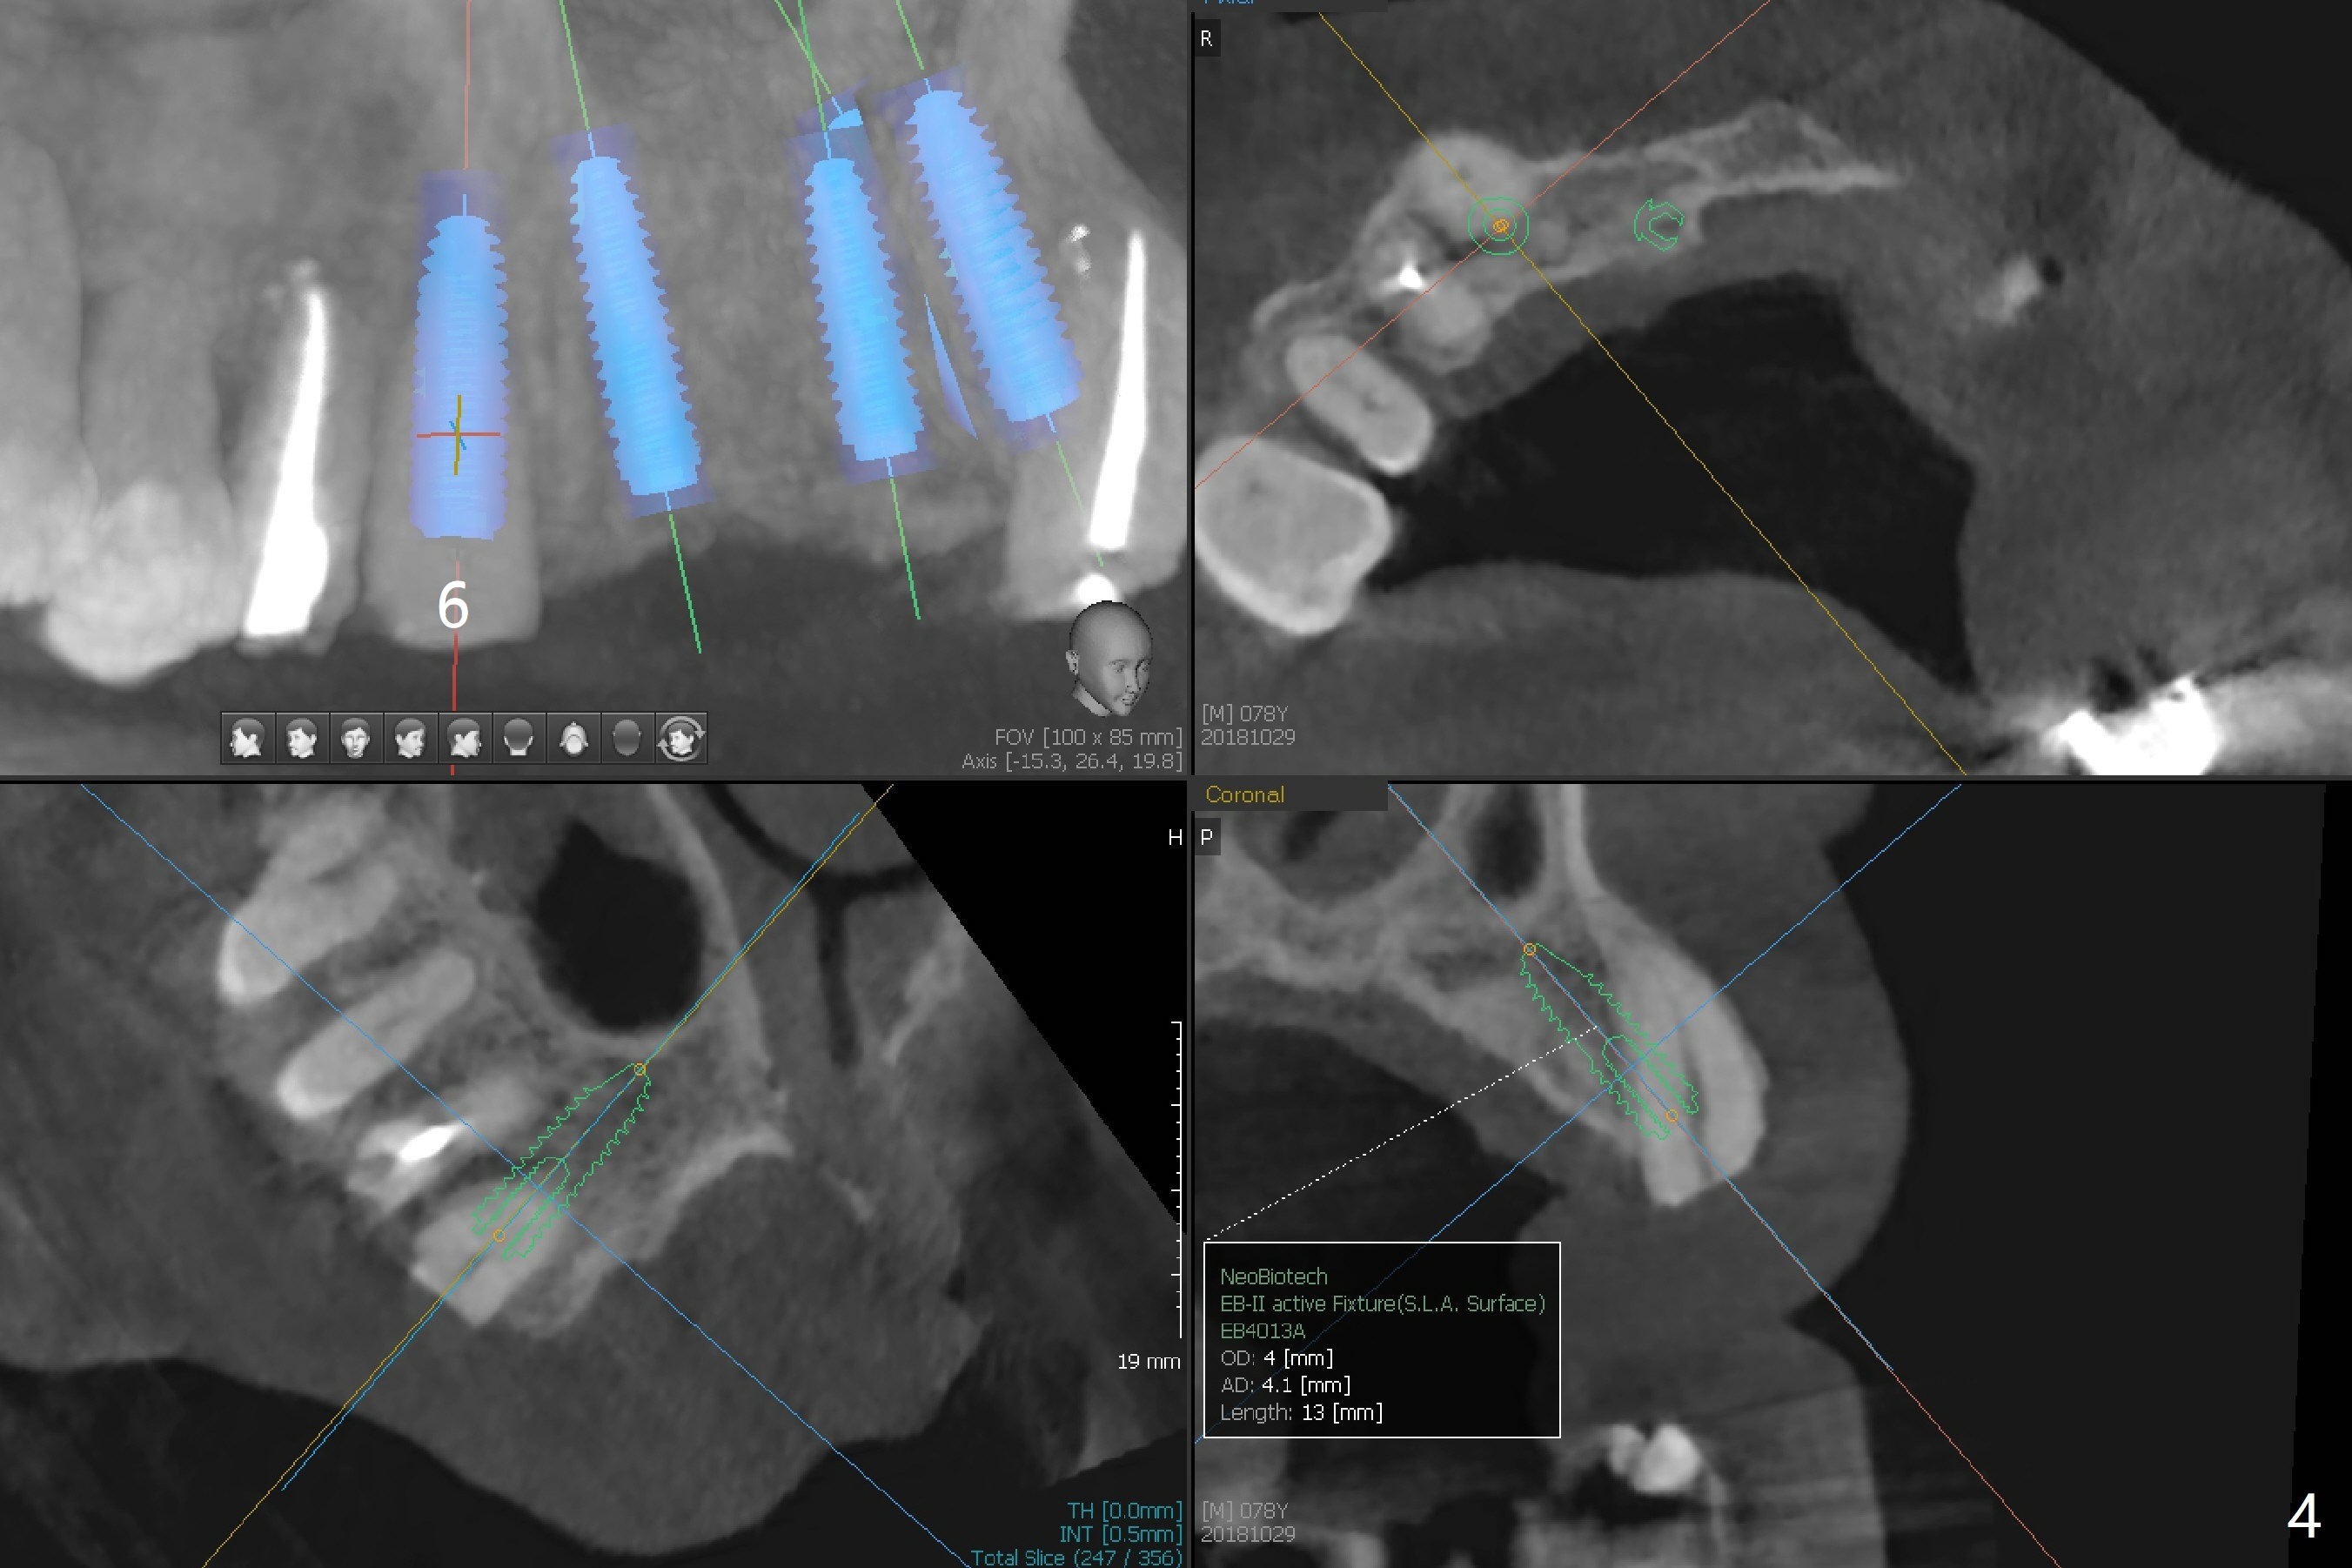

A 78-year-old man's 8 unit FPD dislodges (#5-12, Fig.1). Three of 4 abutments seem to be non-salvageable (#6,11,12 fractured equigingival, extraction, immediate implants). For restoration, implant will be placed at #8 and 9 as well. Implant FPDs will be fabricated at #6-8 and 9-11 (Fig.2) with #5 (with build up or prefabricated post) and 12 single unit crowns to better withstand deep overbite and overjet. After discussion with lab, a major change will be implants to be placed at #7 and 10 instead of #8 and 9 (narrow ridge). The implant at #7 will be a 1-piece (3 mm in diameter), whereas the rest 2-piece (3.5 mm). The abutment of IS 1-piece implant is 10 mm in length, while that of DIO's 5 mm. The former will be used if the vertical space is sufficient.